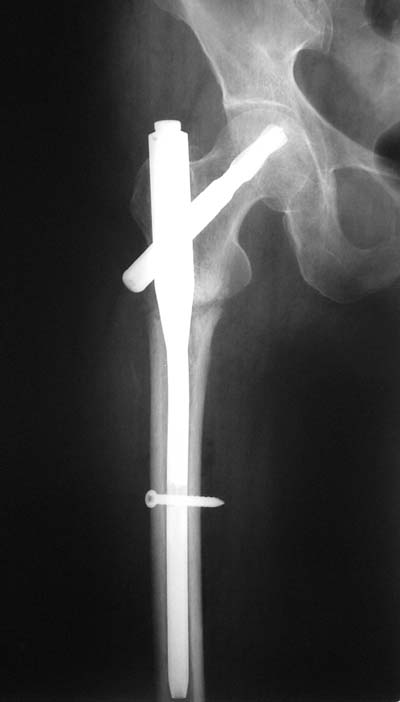

Не думаю так. см вложение.

>> короткий штифт какой-то неуютный выбор.

> Не думаю так. см вложение.

Для такого перелома вполне может быть использован диафизарный штифт, который отечественного производства я даже боюсь считать во сколько раз дешевле... Недавно несколько примеров я закидывал.